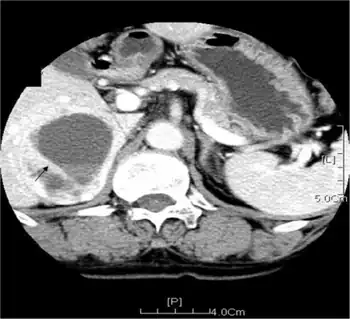

| Bilateral pheochromocytomas associated with Multiple endocrine neoplasia type 2 | |

Pheochromocytoma occurs in 33-50% of MEN2 cases.[5] In MEN2A, primary hyperparathyroidism occurs in 10–50% of cases and is usually diagnosed after the third decade of life. Rarely, it may present in childhood or be the sole clinical manifestation of this syndrome.MEN2A associates medullary thyroid carcinoma with pheochromocytoma in about 20–50% of cases and with primary hyperparathyroidism in 5–20% of cases. MEN2B associates medullary thyroid carcinoma with pheochromocytoma in 50% of cases, with marfanoid habitus and with mucosal and digestive neurofibromatosis.

In familial isolated medullary thyroid carcinoma the other components of the disease are absent. In a review of 85 patients 70 had MEN2A and 15 had MEN2B.[5] The initial manifestation of MEN2 was medullary thyroid carcinoma in 60% of patients, medullary thyroid carcinoma synchronous with pheochromocytoma in 34% and pheochromocytoma alone in 6%. 72% had bilateral pheochromocytomas.